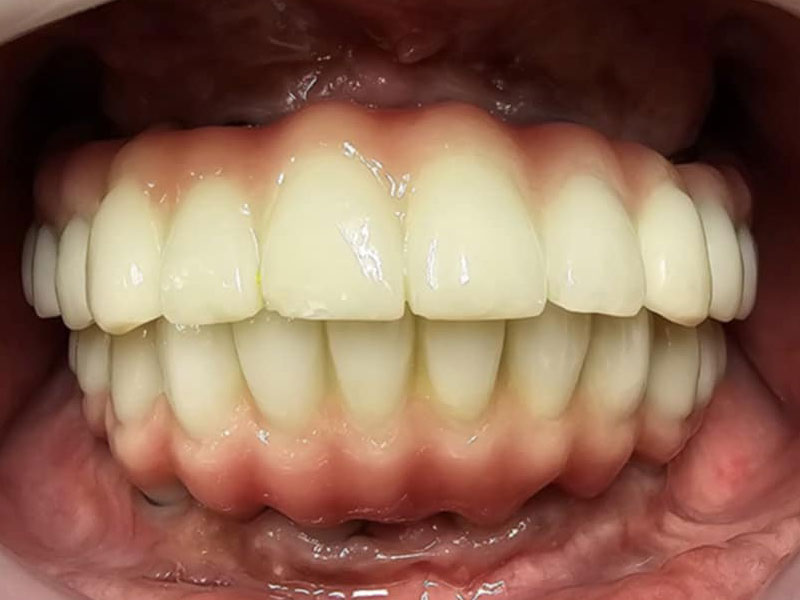

治療後

- 2か月後、抜歯穴の状態が落ち着いてから、最終補綴の型、高さの検査を行い、ねじ止め式の上部構造(チタンフレーム使用+ジルコニア+ガムセラミック)をセット。